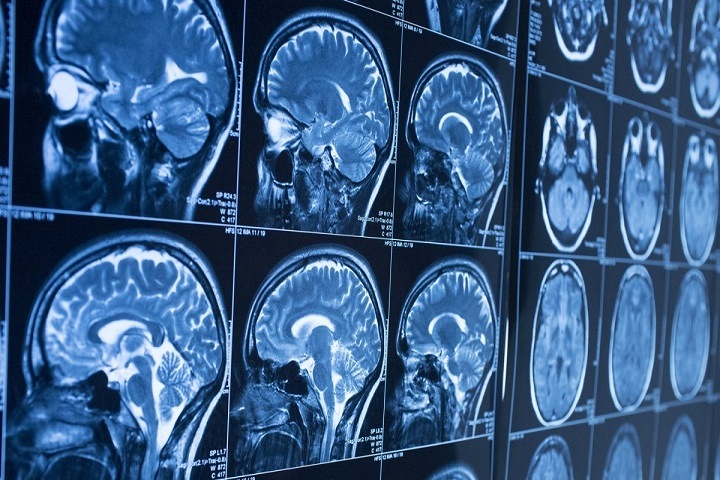

Разработка томских ученых поможет диагностировать злокачественные новообразования. Это позволит визуализировать опухоли головного мозга и персонифицировать объем хирургических вмешательств.

Сейчас в Томском национальном исследовательском медицинском центре вместе с ТПУ ведется разработка радиофармпрепарата «99m Тс-1-тио-D-глюкоза». Он позволит визуализировать опухоли без позитронной эмиссионной компьютерной томографии, а это снизит стоимость процедур.